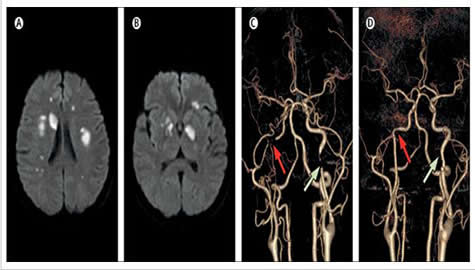

脑卒中是神经科常见疾病,常见的病因包括动脉粥样硬化、高血压、糖尿病及房颤,但对于缺乏以上危险因素的患者,需要仔细寻找病因并给予精准治疗。肖飞副教授在王学峰教授指导下报道了一例急性起病,表现为认知功能下降的一名51岁的中年男性,头颅MRI提示脑梗死,血管影像检查提示双侧颈内动脉狭窄和闭塞,但常规的辅助检查并未发现该患者存在脑血管病常见危险因素。对该患者进行了全面的筛查发现其体内存在明显升高的抗磷脂抗体,其可能引发血管内原位血栓形成,然而单纯表现为双侧颈内动脉狭窄和闭塞的抗磷脂抗体综合征十分罕见。文献报道对于此类患者若给予血管内支架治疗非但不能缓解病情,反而很可能导致支架内血栓形成而加重病情。对该患者启动抗凝治疗,患者症状在3周后明显改善,血管检查提示颈内动脉再通。 近年来,我校王学峰、肖飞课题组依托神经病学国家重点学科、国家临床重点专科及重庆市神经病学重点实验室平台,在癫痫、神经肌肉病及神经疑难罕见病领域开展了深入的临床和基础研究工作,建立了西部地区最大的神经肌肉病和罕见病的临床资料库、组织样本库和基因样本库,取得了突出的成绩。学科疑难罕见病诊治水平得到极大提高,在重庆甚至西部地区首次诊断多种疑难罕见病,居于国内领先水平。课题组在国际上首次报道和总结了中国西部地区NLSDM型肌病患者(目前世界上报道不足50例)的临床、病理和基因突变特点,提出PNPLA2基因的c.757+1G > T是突变热点,具有奠基者效应;在国际上首次报道神经性肌强直作为干燥综合征的罕见神经系统表现;在国内首次报道青少年起病的成人型神经元蜡样脂褐素沉积症(Kufs病),提出皮肤肌肉及血液白细胞的特殊病理染色能够快速、准确诊断本病;发现并报道中国西部首例齿状核红核苍白球路易体萎缩(DRPLA)患者。课题组根据以上成果,由肖飞副教授作为第一作者,在王学峰教授指导下完成多篇学术论文,发表在国际著名神经病学期刊JAMA Neurology (IF=11.46), Neurology (2篇,IF= 7.6 )等。